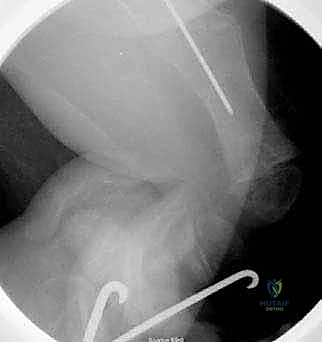

قبل العملية، يقوم الدكتور هطيف بإجراء دراسة شاملة لصور الأشعة السينية (X-rays) المأخوذة بدقة، لحساب زوايا التقوس بدقة متناهية، وتحديد نقاط بضع العظم (أماكن القص)، واختيار الحجم والطول المناسبين للمسمار التلسكوبي.

يتم إجراء العملية تحت التخدير العام. يتم وضع الطفل على طاولة العمليات الشفافة للأشعة، ويتم استخدام جهاز الأشعة السينية المستمر (C-arm) لضمان الدقة المطلقة خلال كل ثانية من العملية.

- يتم إجراء أشعة سينية للتأكد من بدء تكوّن الدشبذ العظمي (Callus) حول مناطق القص.